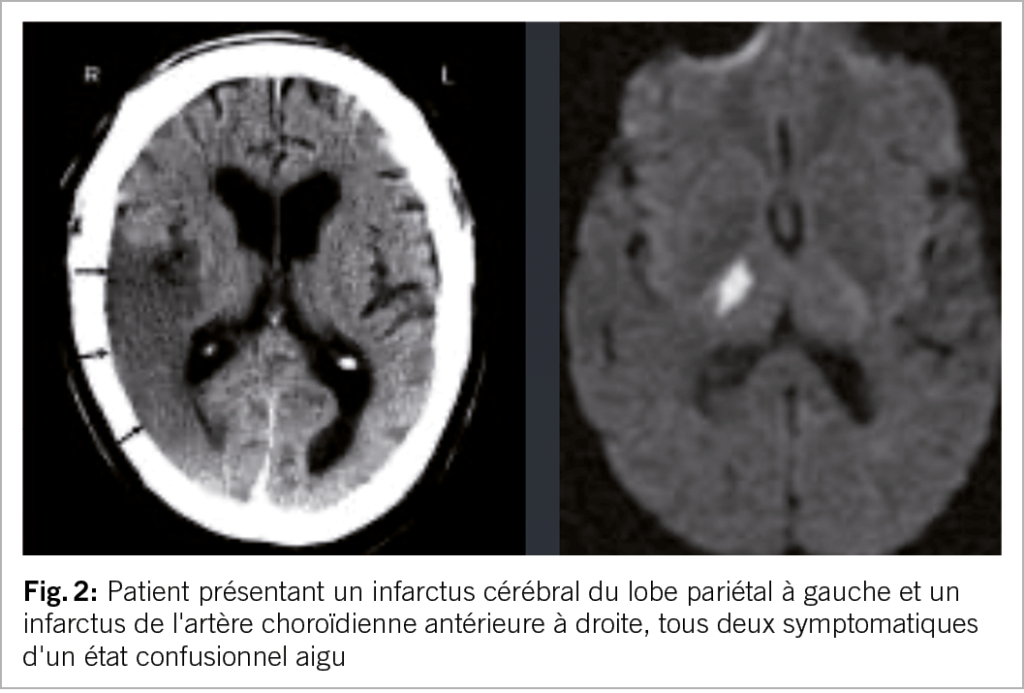

Les AVC peuvent s’accompagner de confusion, d’ excitation ou d’ agitation et être pris à tort pour un délire. Les infarctus du lobe pariétal ou ceux au niveau du territoire de l’artère choroïdienne antérieure sont typiques et peuvent provoquer une confusion aiguë. Un indice clinique utile est l’ apparition soudaine de la confusion (phase très aiguë) chez un patient auparavant asymptomatique (fig. 2).